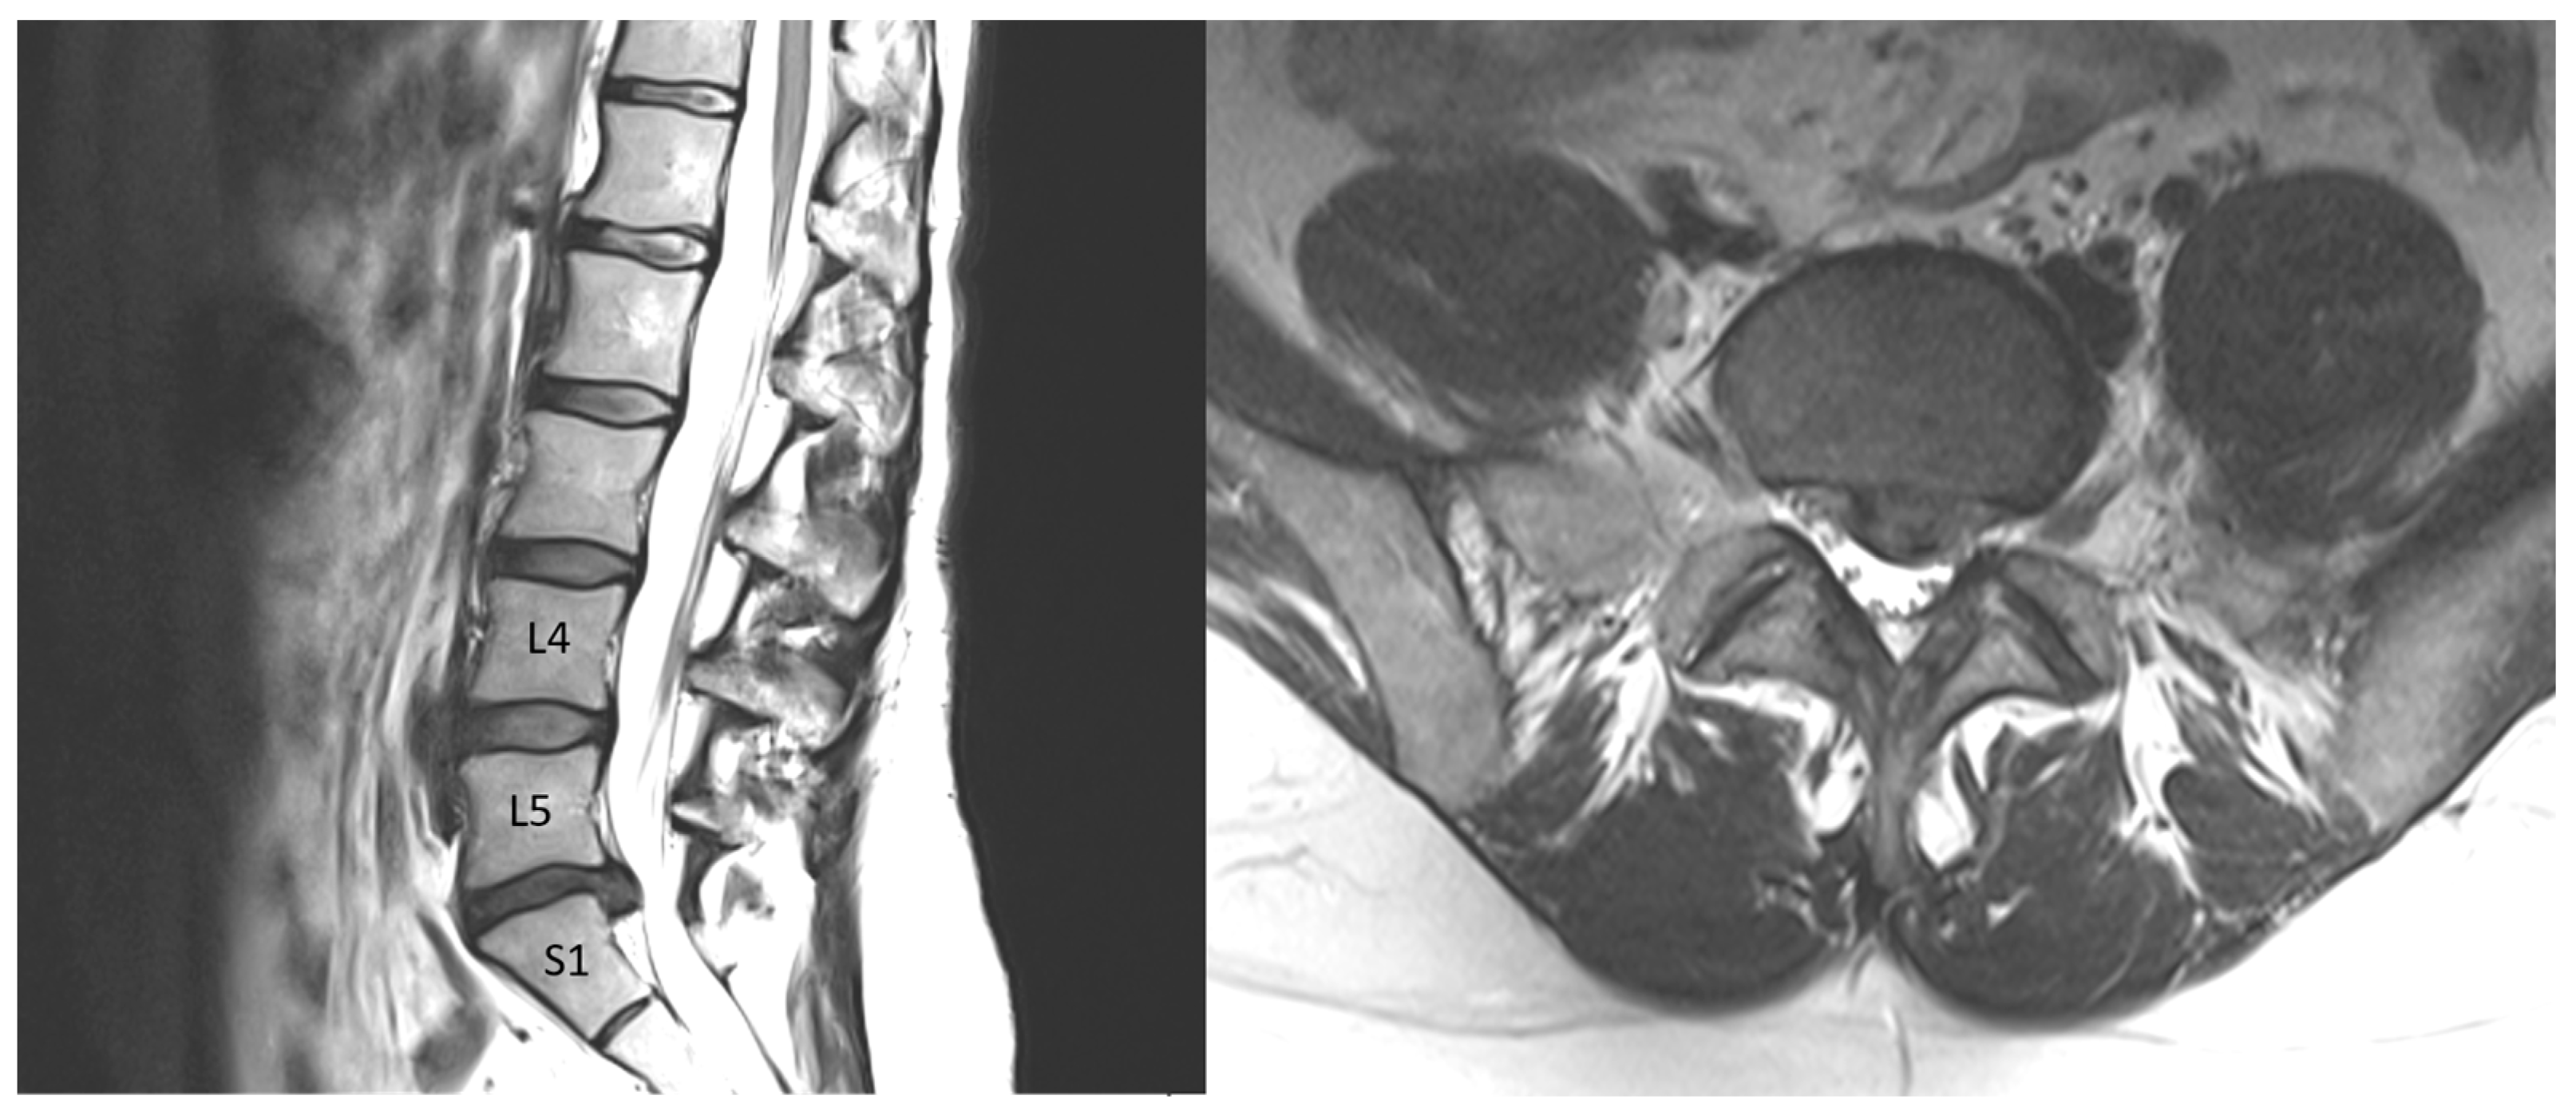

A 36-year-old female was admitted to the hospital because of sciatica pain lasting 3 months in the right leg. Routine clinical tests, such as blood morphology and sodium, potassium, chloride, creatinine, and glucose levels, as well as tests of the coagulation system and autoimmunology and rheumatology tests, were performed on the patient before surgery and were within the normal range for age and gender. The symptoms did not subside after conservative treatment. MRI (Figure 4) revealed prolapse at the L5/S1 level of the spine in a degenerated disc (grade IV on the Pfirrmann scale—an inhomogeneous hypointense dark gray disc with significant disc height loss). Minimally invasive discectomy via microscopy was performed. Because the disc tissue had atypical, soft consistency, an additional intraoperative X-ray was performed, and it was noted that the discoidectomy was mistakenly performed at the L4/5 level (grade II on the Pfirrmann scale—an inhomogeneous disc with normal disc height and a clear difference between the nucleus and annulus). An error was noticed, and fenestration with the removal of the disc at the level of L5/S1 from the right side was performed. Careful hemostasis prevented contamination of the tissue with blood. After the procedure, the patient was informed about the course of the procedure and gave her written consent for the examination of the collected tissue from both levels. Recently, the patient has felt well. The disc at level L5/S1 was assigned as a surgical disc and at level L4/5 as a nonsurgical disc.

Figure 4.

T2-weighted images in sagittal and axial projections. At the L4/5 level, control disc, and at the L5/S1 level, visible left-sided protrusion of dehydrated disc.